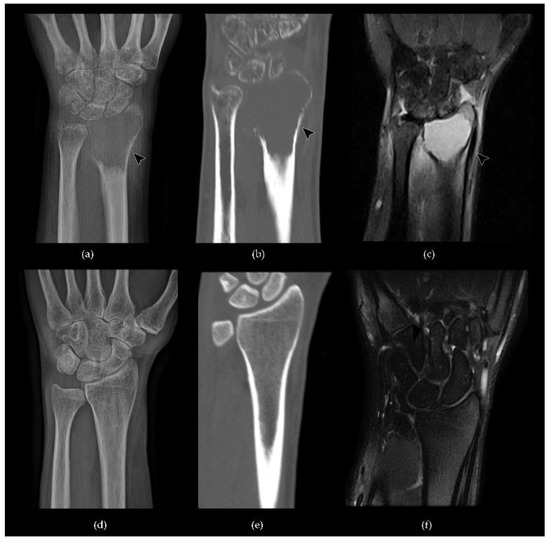

- Murphey, M.D.; Nomikos, G.C.; Flemming, D.J.; Gannon, F.H.; Temple, H.T.; Kransdorf, M.J. From the archives of the AFIP. Imaging of giant cell tumor and giant cell reparative granuloma of bone: Radiologie-pathologic correlation. Radiographics 2001, 21, 1283–1309. [Google Scholar] [CrossRef] [PubMed]

- Chakarun, C.J.; Forrester, D.M.; Gottsegen, C.J.; Patel, D.B.; White, E.A.; Matcuk, G.R. Giant cell tumor of bone: Review, mimics, and new developments in treatment. Radiographics 2013, 33, 197–211. [Google Scholar] [CrossRef]

- Woertler, K. Benign bone tumors and tumor-like lesions: Value of cross-sectional imaging. Eur. Radiol. 2003, 13, 1820–1835. [Google Scholar] [CrossRef]

- Pereira, H.M.; Marchiori, E.; Severo, A. Magnetic resonance imaging aspects of giant-cell tumours of bone. J. Med. Imaging Radiat. Oncol. 2014, 58, 674–678. [Google Scholar] [CrossRef]

- Aoki, J.; Tanikawa, H.; Ishii, K.; Seo, G.S.; Karakida, O.; Sone, S.; Ichikawa, T.; Kachi, K. MR findings indicative of hemosiderin in giant-cell tumor of bone: Frequency, cause, and diagnostic significance. AJR Am. J. Roentgenol. 1996, 166, 145–148. [Google Scholar] [CrossRef]